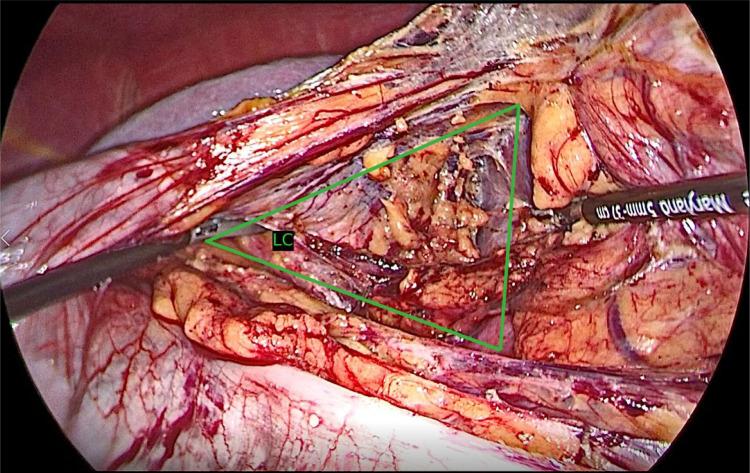

Objective: Laparoscopic donor nephrectomy has become a standard of care for living kidney donors, providing reduced morbidity, quicker recovery, and enhanced patient satisfaction compared with open techniques. This study evaluates a modified laparoscopic donor nephrectomy technique designed to minimize colon mobilization while optimizing visualization, thereby improving donor outcomes. Methods: A cross-sectional study of 250 consecutive living donor nephrectomies performed by a single surgeon between March 2022 and March 2024 was conducted. All donors underwent preoperative imaging (3D computed tomography and computed tomographic angiography). The modified approach avoided splenic flexure dissection and introduced early ligation of the adrenal vein. We analyzed intraoperative parameters (operative time, estimated blood loss, complications) and postoperative measures (hospital stay, pain scores, complication rates, satisfaction) were analyzed. Results: The mean operative time was 72.8 ± 16.2 minutes, with an estimated blood loss of 100 ± 40 mL. No conversions to open surgery or intraoperative transfusions were required. The mean length of hospital stay was 2.0 ± 1.0 days. Postoperative pain (mean Visual Analog Scale [VAS] 2.5 ± 1.8) was low, and major vascular injury occurred in 0.8% of cases. Wound infection and incisional hernia rates were each 0.8%. Patient satisfaction was high (Patient Satisfaction Questionnaire [PSQ] 3.3 ± 1.4), indicating favorable perceptions of comfort and outcomes. Conclusion: This modified laparoscopic donor nephrectomy technique is safe, effective, and associated with enhanced patient comfort and reduced complications. The findings underscore its potential to improve donor experiences, potentially expanding the living donor pool. Further investigations should confirm these outcomes over a longer follow-up period.

目的